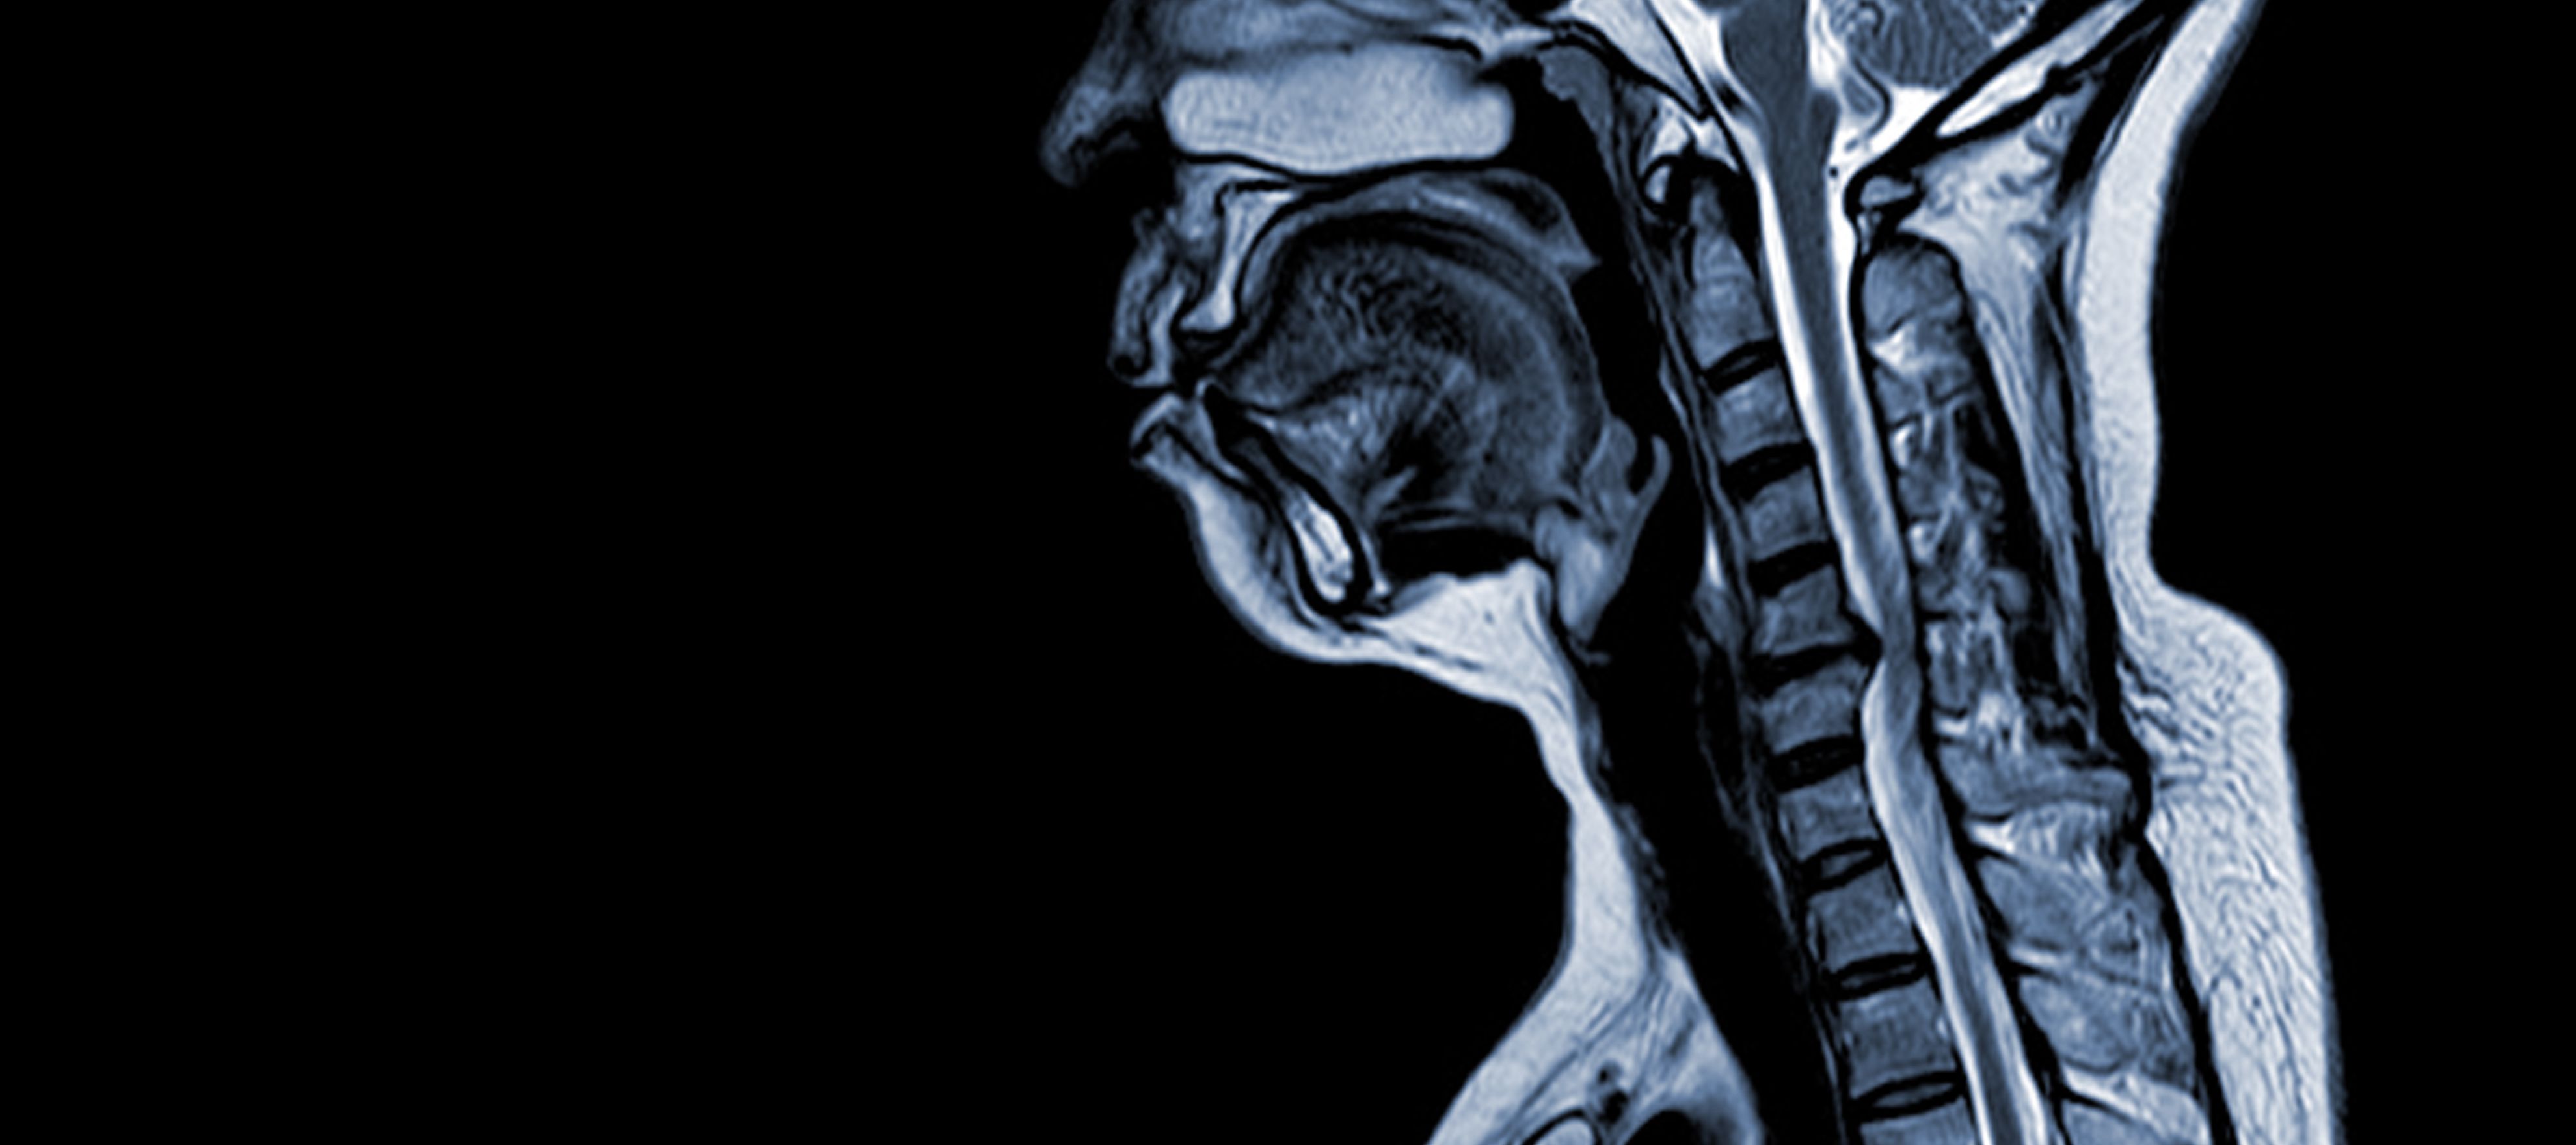

Cervikal spondylotisk myelopati (CSM) er en neurologisk tilstand, som er den hyppigste årsag til rygmarvsskader hos voksne. Enkelt sagt er der tale om kompression eller beskadigelse af rygmarven i nakken, primært på grund af den naturlige aldringsproces, der påvirker halshvirvlerne. Udtrykket 'myelopati' stammer fra de græske ord 'myelon', som betyder 'rygmarv' og 'pathos', som betyder 'sygdom'.

Patofysiologi

- Degeneration af diskus (udbuling af diskus): CSM begynder ofte med degeneration af intervertebrale skiver i halshvirvelsøjlen, hvilket får dem til at bule ud eller stikke ind i rygmarvskanalen.

- Subperiostal knogledannelse (ventral for rygmarvskanalen): Som reaktion på den øgede mekaniske belastning danner kroppen nyt knoglevæv på den forreste (ventrale) side af rygmarvskanalen, hvilket potentielt indsnævrer pladsen til rygmarven.

- Ossifikation af posterior longitudinal ligament: Det bageste langsgående ledbånd kan forbenes, hærdes og forkalkes, hvilket bidrager til indsnævring af rygmarvskanalen.

- Hypertrofi af Ligamentum Flavum: Hypertrofi af Ligamentum Flavum får det til at blive tykkere og mindre fleksibelt, hvilket yderligere indskrænker pladsen i rygmarvskanalen og komprimerer rygmarven.

Disse strukturelle ændringer fører samlet set til kompression og indsnævring af rygmarvskanalen, hvilket resulterer i de karakteristiske symptomer og komplikationer, der er forbundet med CSM. Anerkendelse af disse risikofaktorer og forståelse af de patofysiologiske mekanismer, der er involveret, er afgørende for både forebyggelse og behandling. Tidlig diagnose og passende indgreb er afgørende for at afbøde virkningerne af disse strukturelle ændringer på rygmarven.